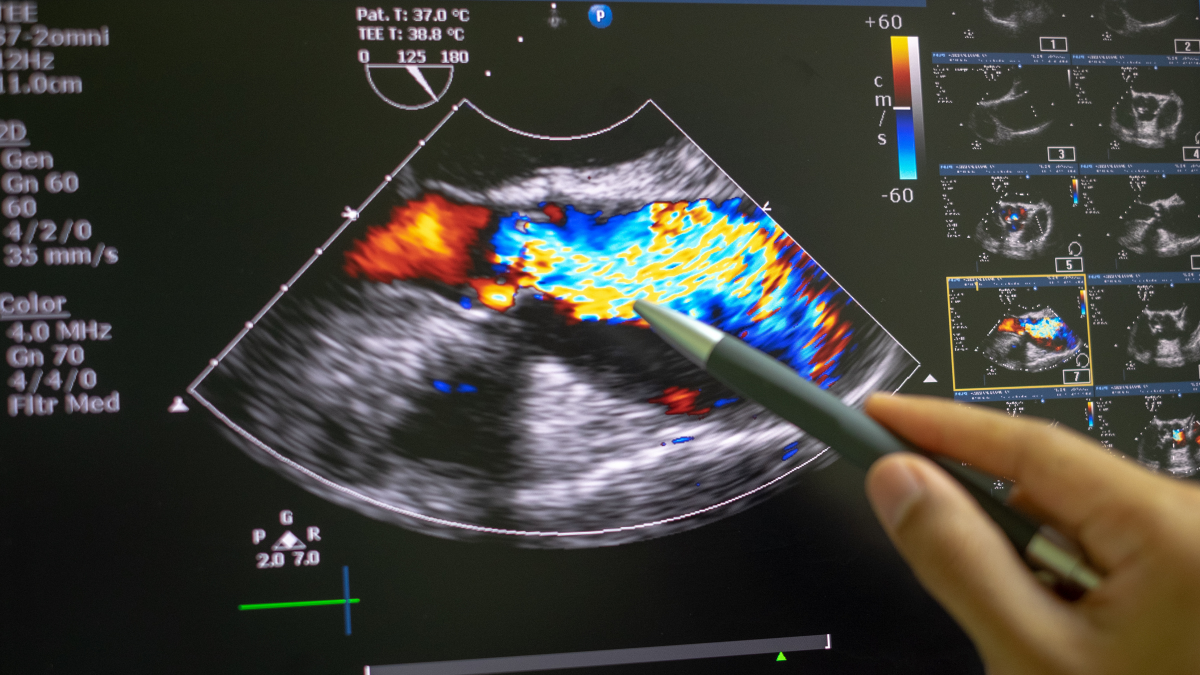

Echocardiography Essentials for Monitoring Heart Health

Echocardiography is a non-invasive ultrasound test used to evaluate heart health by producing images…